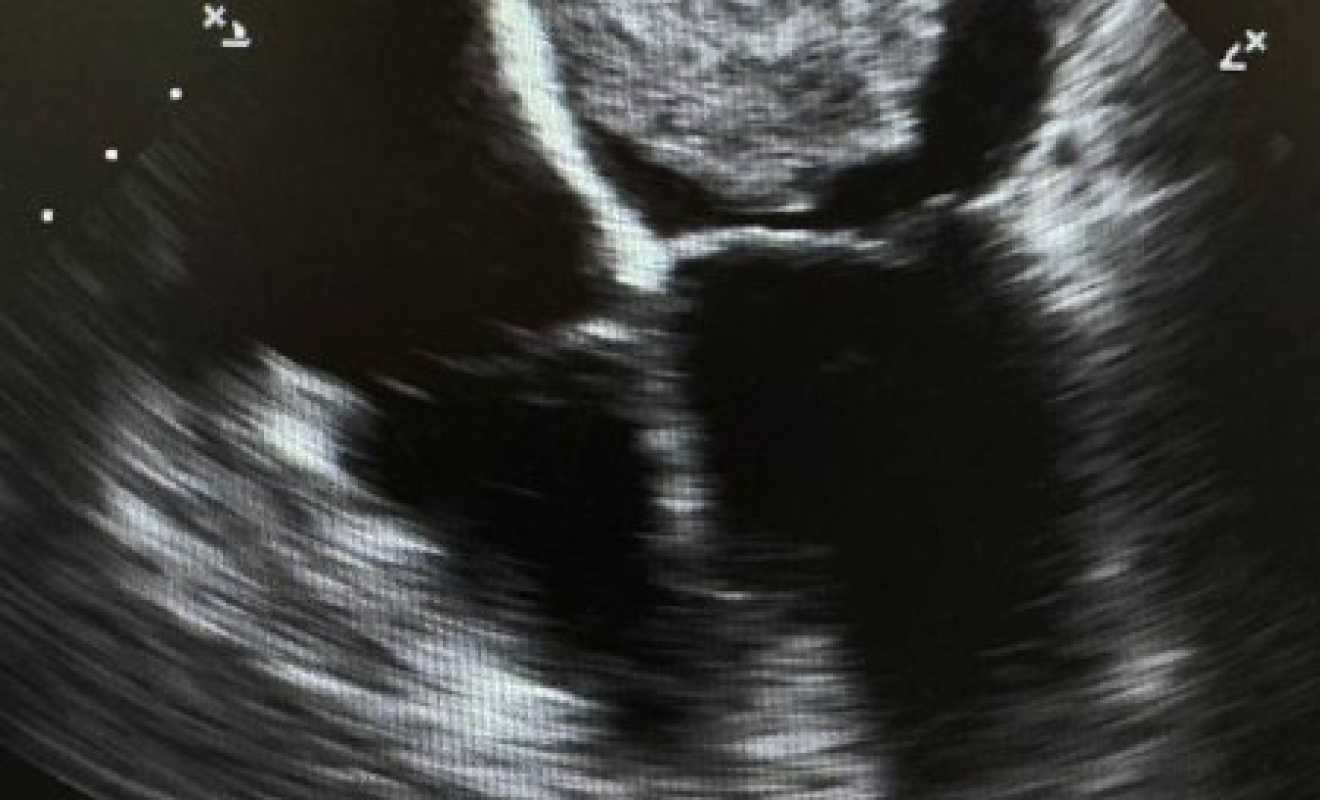

В Дагестане врачи удалили женщине опухоль сердца размером с теннисный мяч

Операцию провели специалисты республиканского центра кардиологии и сердечно-сосудистой хирургии.

Пациентку 55-ти лет перед операцией в течение двух лет беспокоила одышка.

При обследовании у врачей причина одышки оставалась неясной, в сентябре 2026 года состояние здоровья дагестанки резко ухудшилось. Женщина стала сильно задыхаться даже при небольших физических нагрузках. УЗИ сердца показало опухоль органа – миксому, а также недостаточность митрального и трикуспидального клапанов.

Образование на сердце оказалось размером 6,5x4,6 см.

Как рассказали в минздраве региона, в декабре больную госпитализировали и удалили опухоль, которая к тому моменту достигла размера 10x12 см. Кроме того, женщине выполнили протезирование митрального клапана и пластику трикуспидального.

В ведомстве заверили, что сейчас пациентка чувствует себя удовлетворительно, получает терапию и готовится к выписке.